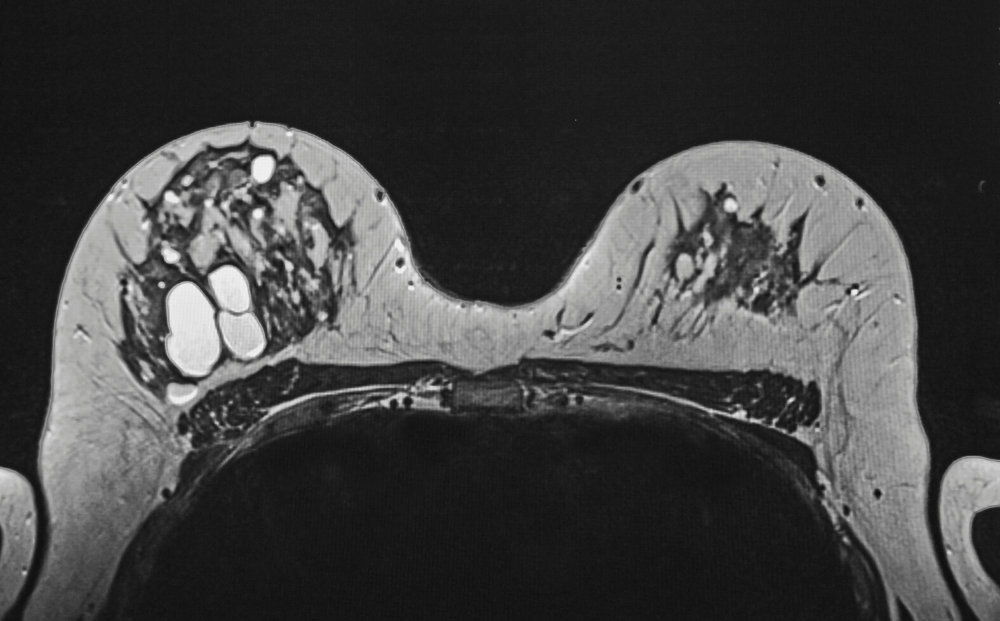

A sebaceous cyst is a bump that develops under the human skin. They are also known as keratin cyst or epidermoid cyst. They develop and after few days vanish by themselves. Sebaceous cysts are caused due to blockage of sebaceous gland by a protein called keratin. Sebaceous cysts can sometimes have a pungent odor as they contain yellow clear oily liquid. They may occur all over our body, except soles of palm and feet. Sebaceous cysts mostly occur on head, back, breast and face. They vary in size and are mostly not harmful and are non cancerous. They appear as a result of swollen hair follicle. There are many methods of sebaceous cysts treatment. However, you must know what are the causes sebaceous cysts.